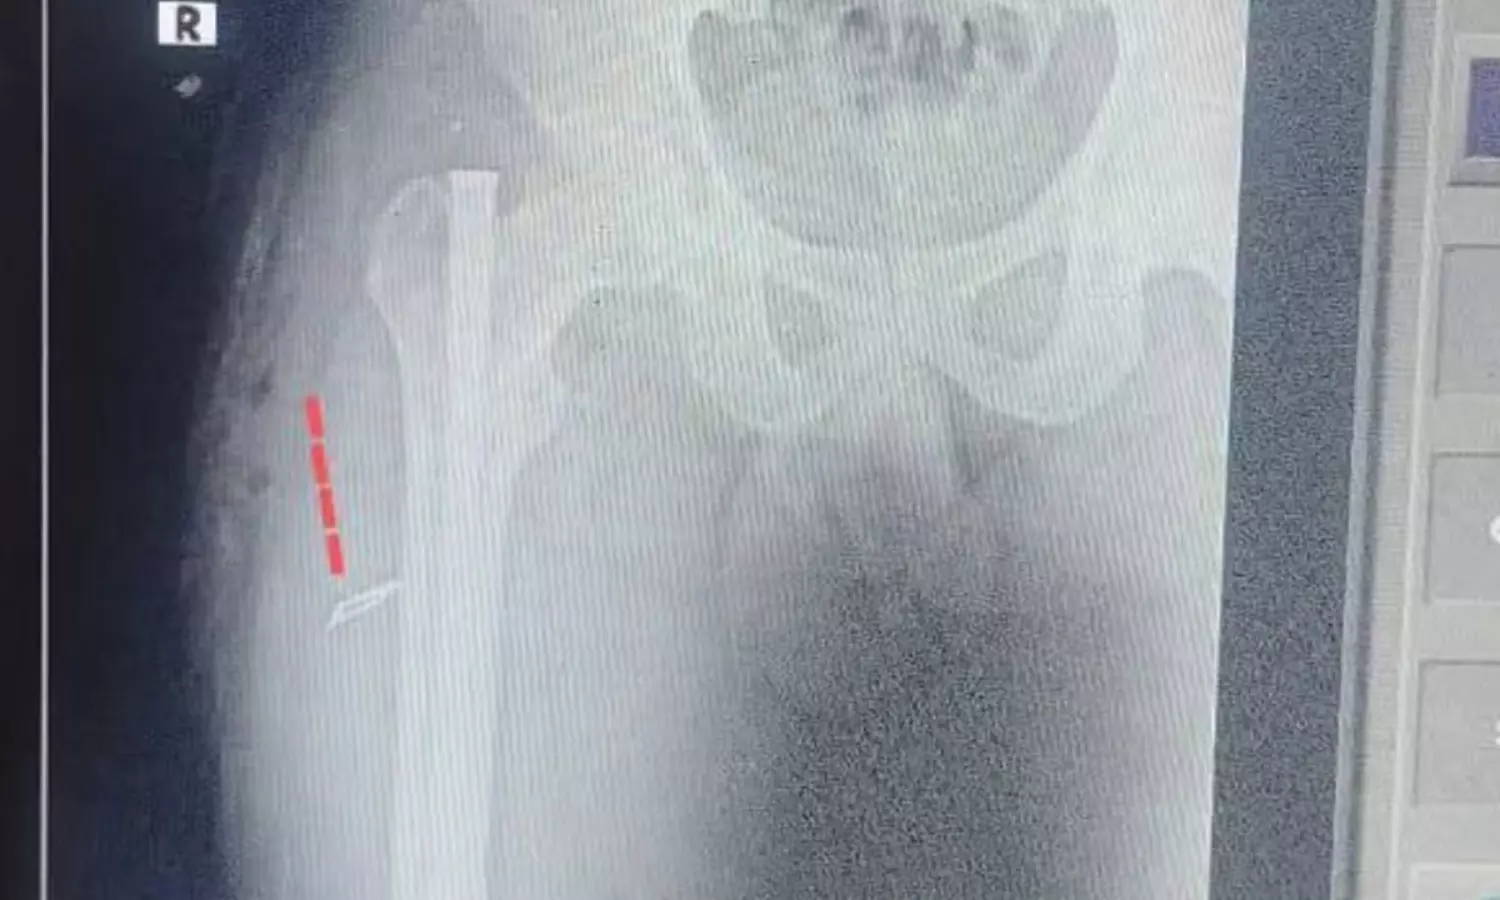

ఎక్స్ రే ద్వారా తేలింది :

అయితే తన కడుపులో బ్లేడ్ ఉన్నట్లుగా ఎక్స్ రేలో తేలింది. దీంతో ఈ వార్త వెలుగు చూడడంతో విధుల నిర్వహణలో బాధ్యతారాహిత్యంగా వ్యవహరించిన వైద్య సిబ్బంది నిర్లక్ష్యంపై మంత్రి సత్యకుమార్ యాదవ్ తీవ్ర ఆగ్రహం వ్యక్తం చేశారు. ఈ ఘటన మీద విచారణ జరిపి నివేదించాలని డైరెక్టర్ ఆఫ్ సెకండరీ హెల్త్ విభాగాన్ని ఆదేశించారు. ఈ మేరకు అయన విచారణ జరిపించారు. తద్వారా వైద్యుడు స్టాఫ్ నర్సు శస్త్రచికిత్స సమయంలో బాధ్యతారాహిత్యంగా వ్యవహరించినట్లు తేలింది అని నివేదిక వచ్చింది. ఈ క్రమంలో వారి మీద సస్పెన్షన్ వేటు పడింది.